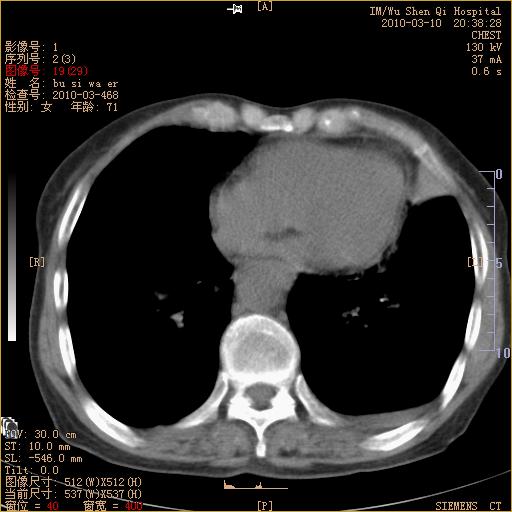

以下是引用随光逐影在2010-3-11 0:41:00的发言:[br]1)考虑左肺及右肺上叶继发性肺结核并左肺炎症感染。2)左侧支气管内膜结核可能;建议必要时行纤支镜检查。3)肺气肿。4)心包膜增厚(或少量心包积液)。5)左侧胸腔积液。